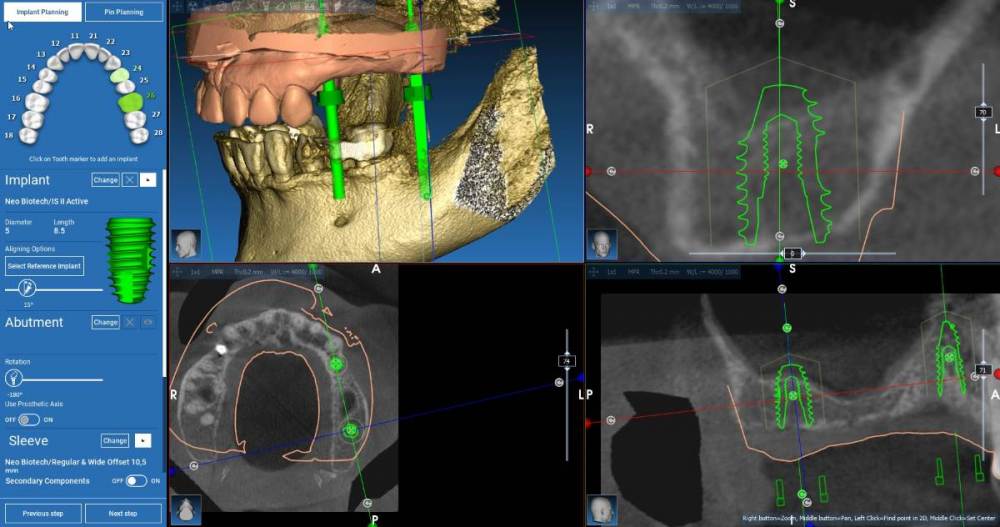

Fin Опубликовано 7 мая, 2021 Поделиться Опубликовано 7 мая, 2021 Здравствуйте коллеги. Прошу Вашего совета по поводу одного клинического случая. У пациентки отсутствуют зубы с 2.4 до 2.7. Хочу восстановить данный дефект 2мя импл.,и обойтись без ОСЛ. Поэтому в обл.2.6(2.7) хочу поставить импл.8.5х5(5.5) в обл. 2.4 - 3.5х10. . Возник вопрос как лучше поставить импл. в обл 3.6 под углом с небольшим ЗСЛ и протезированием при помощи МЮ или без угла с ЗСЛ (но ЗСЛ скорее всего будет с графтом) Ссылка на комментарий